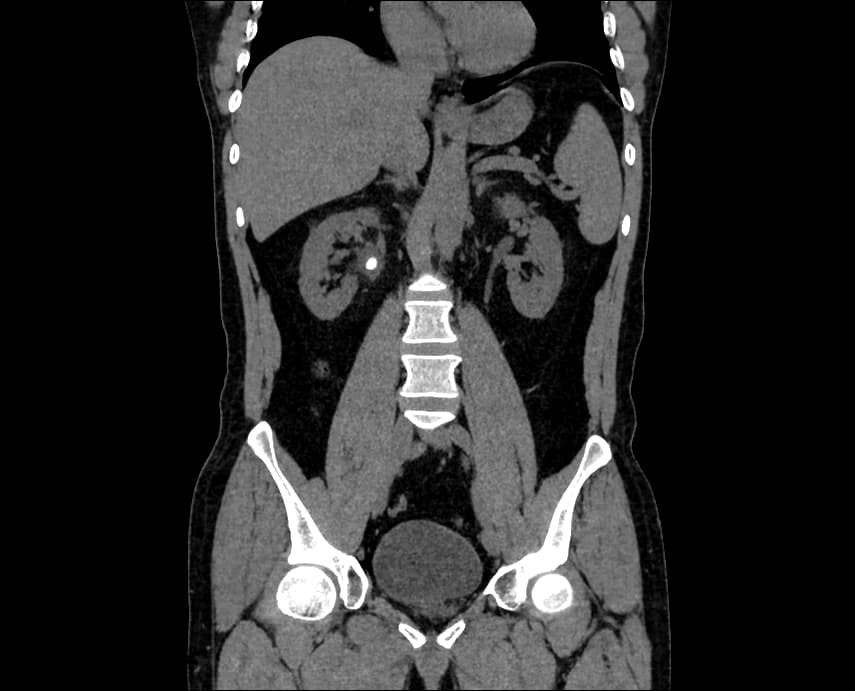

Segment Kidney Tumor from CT Images

Advanced AI techniques enable the precise segmentation of kidney tumors in CT scans. This solution enhances the clarity and accuracy of tumor visualization, assisting medical professionals in developing targeted treatment strategies.